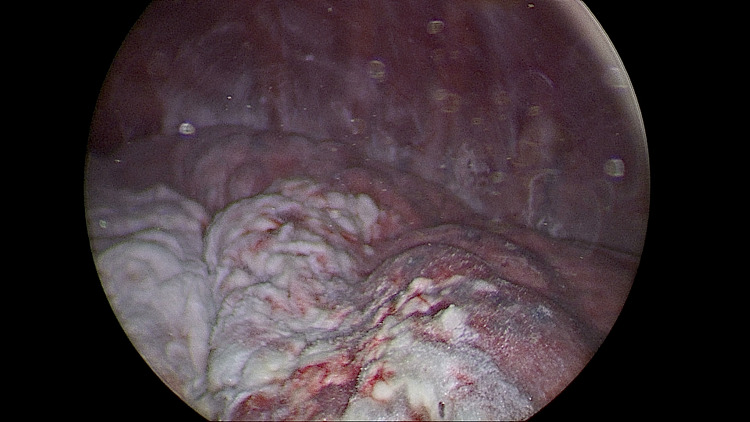

Introduction: Medical thoracoscopy is a minimally invasive and safe procedure mostly performed for unexplained exudative pleural effusions but may be considered for pneumothorax (PNX).

Methods: This retrospective study included participants affected by PNX who underwent medical thoracoscopy with talc poudrage at a single academic hospital from 2008 to 2021. The primary endpoint was the observation of complete radiographical lung re-expansion and absence of air supply from the chest drain within 7 days of medical thoracoscopy. The secondary endpoint was achieving no recurrence of ipsilateral PNX at 24 months post-discharge.

Results: A total of 95 patients affected by primary spontaneous PNX (PSP), secondary spontaneous PNX (SSP), iatrogenic, and traumatic PNX were enrolled. An additional procedure was required by 17.89% of patients, and only one patient with SSP required subsequent surgery. Recurrence of PNX occurred on the same side within 24 months after discharge in 9.47% of patients, with a median time to recurrence of 13.5 months. The PSP group was significantly more likely to achieve the primary endpoint. Pleural morphology was significantly associated with reaching the primary endpoint, while receiving a cumulative dose of talc greater than or equal to 4 g during hospitalization was associated with a lower risk of meeting it. Receiving a cumulative dose of talc greater than or equal to 4 g led in all cases to the achievement of the secondary endpoint. Patients with iatrogenic and traumatic PNX had an excellent prognosis in both the short- and long-term evaluation.

Conclusion: Medical thoracoscopy is an effective procedure for treating PNX in the acute setting in selected cases while preventing long-term relapses. Large prospective clinical studies are needed to support and better define the role of medical thoracoscopy in current clinical practice.